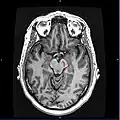

Horizontal MRI (T1 weighted) slice with highlighting indicating location of the substantia nigra. -